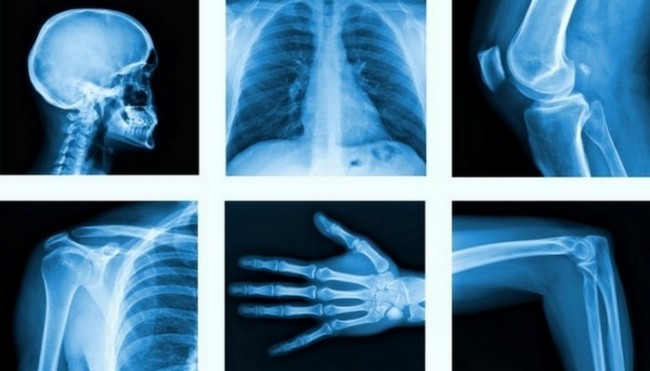

2. X-ray

Today, it is difficult to imagine the diagnosis and proper treatment of injuries such as bone fractures without X-ray imaging technology. X-ray radiation was discovered by the German physicist Wilhelm Konrad von Röntgen accidentally while studying the passage of an electric current through a gas at ultra-low pressure.

The scientist noticed that an electron beam tube coated with barium platinum cyanide was illuminating the darkened room with fluorescent light. Since the cathode rays were invisible, he did not know what rays were emitting such light, and he called them X-rays. The scientist was awarded the Nobel Prize in physics for his invention in 1901 for the first time in history.